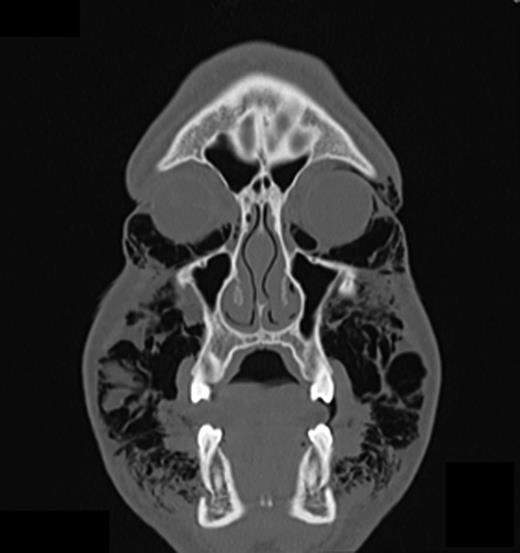

Computed tomography (CT) of the head and neck region revealed a bilaterally located subcutaneous air collection in the area of the periorbital, temporal, paramandibular and supraclavicular region (Figs 3–5). There were no signs or symptoms of severe complications such as pneumothorax or pneumomediastinum.

CT scan (coronal section in the first premolar region) showing multiple air inclusions within the facial soft tissue.